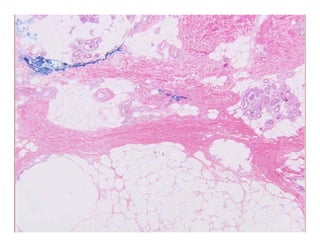

Calcifying panniculitisCalcifying panniculitisCalcifying panniculitisCalcifying panniculitis

CalciphylaxisCalciphylaxis

R lifR lif th t i dth t i d–– Rare, lifeRare, life--threatening syndromethreatening syndrome

–– Progressive microvascular and superficial soft tissue calcificationProgressive microvascular and superficial soft tissue calcification

–– Setting of secondary hyperparathyroidism and chronic renal failureSetting of secondary hyperparathyroidism and chronic renal failure

–– Painful violaceous skin lesions that progress to nonhealing ulcers withPainful violaceous skin lesions that progress to nonhealing ulcers with

underlying tissue necrosisunderlying tissue necrosis

–– Many complications…mortality >60%Many complications…mortality >60%

–– Histology:Histology:

Intravascular calcium deposits within small and mediumIntravascular calcium deposits within small and medium--sized vesselssized vessels

Also within extravascular soft tissues and visceraAlso within extravascular soft tissues and viscera

May have endovascular fibroblasticMay have endovascular fibroblastic intimal proliferation luminal thrombosisintimal proliferation luminal thrombosisMay have endovascular fibroblasticMay have endovascular fibroblastic--intimal proliferation, luminal thrombosis,intimal proliferation, luminal thrombosis,

or calcific obliteration of vesselsor calcific obliteration of vessels

“Clean” necrosis“Clean” necrosis

–– RelativelyRelatively scantscant inflammationinflammation